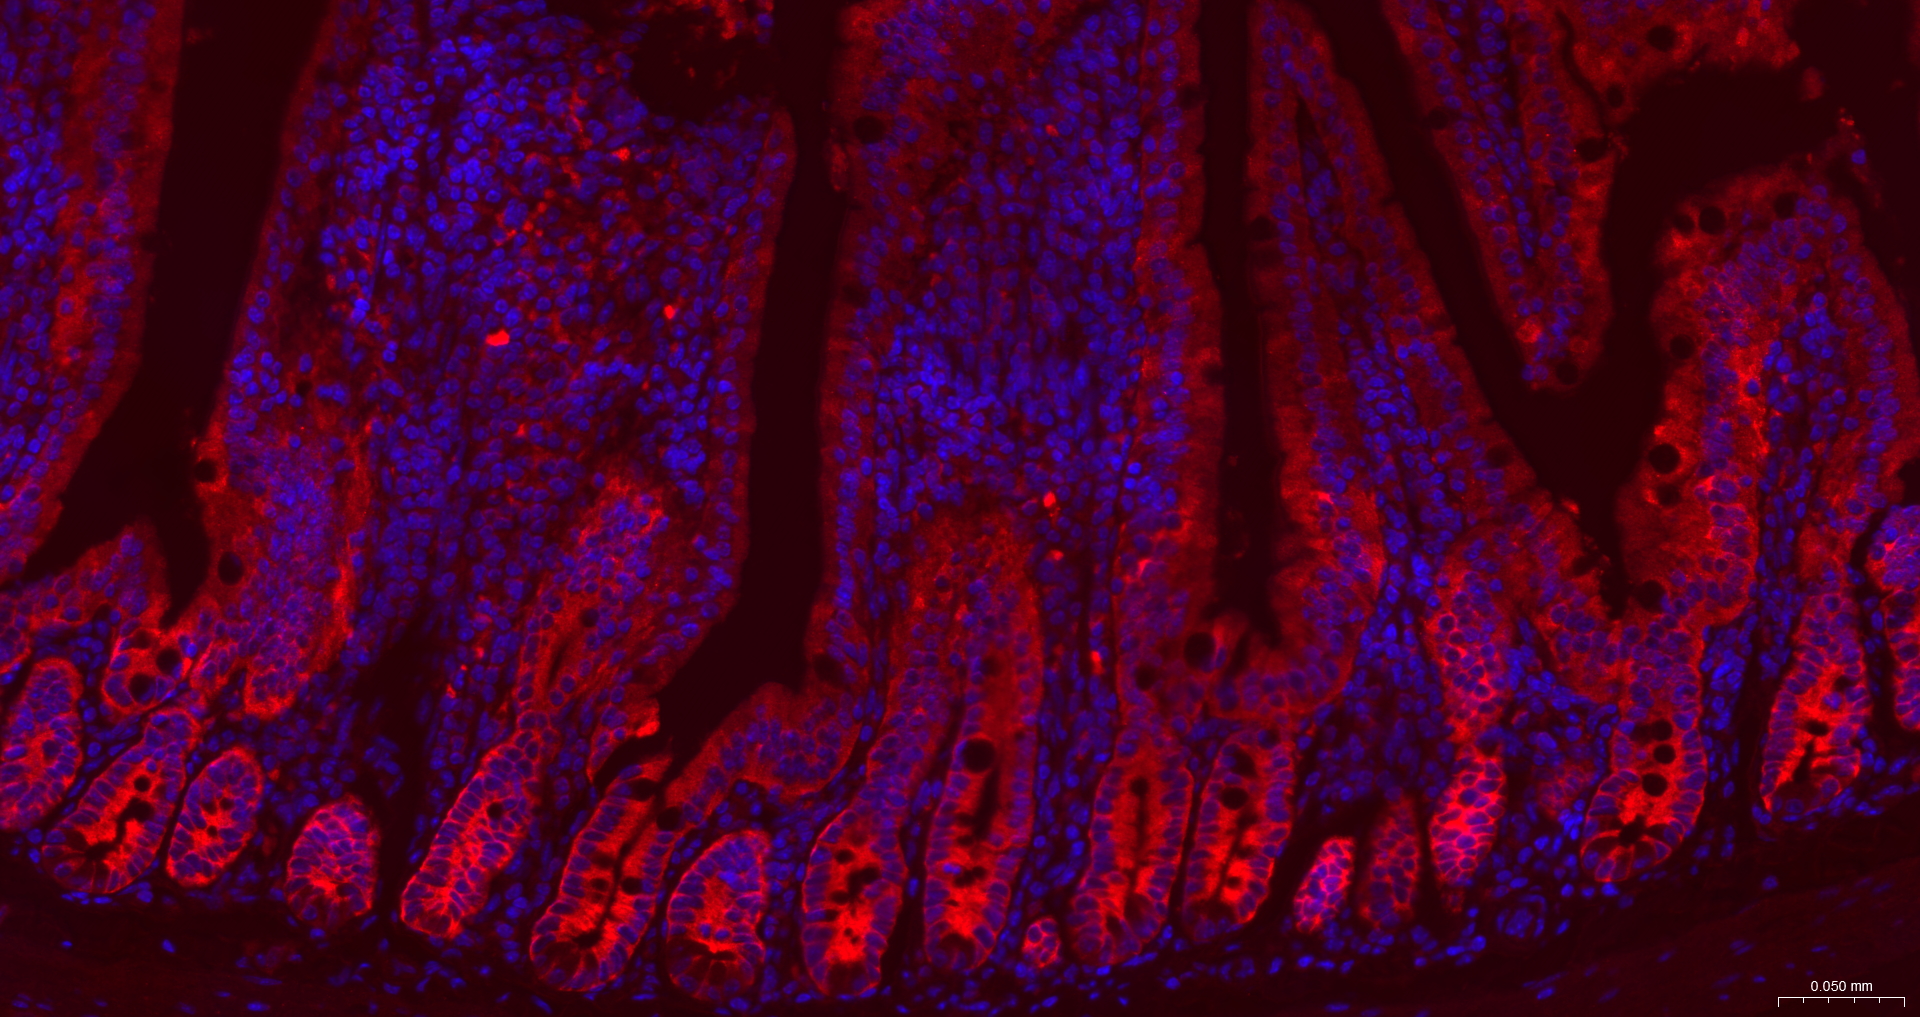

IF(ICC) IFICC1:50-200